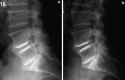

A retrospective clinical-radiological study to evaluate the long-term outcome after artificial disc replacement was performed. The objective is to investigate long-term results after implantation of a modular type artificial disc prosthesis in patients with degenerative disc disease (DDD). Total disc replacement (TDR) is a surgical procedure intended to save segmental spinal function, and thus replace spondylodesis. Short-term results are promising, whereas long-term results are scarce. The Charité TDR is the oldest existing implant, therefore, the longest possible follow-up is presented here. Seventy-one patients were treated with 84 Charité TDRs types I-III. Indication for TDR was moderate to severe DDD. Fifty-three patients (63 TDRs) were available for long-term follow-up of 17 years. Evaluation included Oswestry disability index, visual analog scale, overall outcome score, plain and extension/flexion radiographs. Implantation of Charité TDR resulted in a 60% rate of spontaneous ankylosis after 17 years. No significant difference between the three types of prostheses was found concerning clinical outcome. Reoperation was necessary in 11% of patients. Although no adjacent segment degeneration was observed in the functional implants (17%), these patients were significantly less satisfied than those with spontaneous ankylosis. TDR, nowadays, is an approved procedure. Proof that long-term results of TDR implantation in DDD are at least as good as fusion results is still missing.